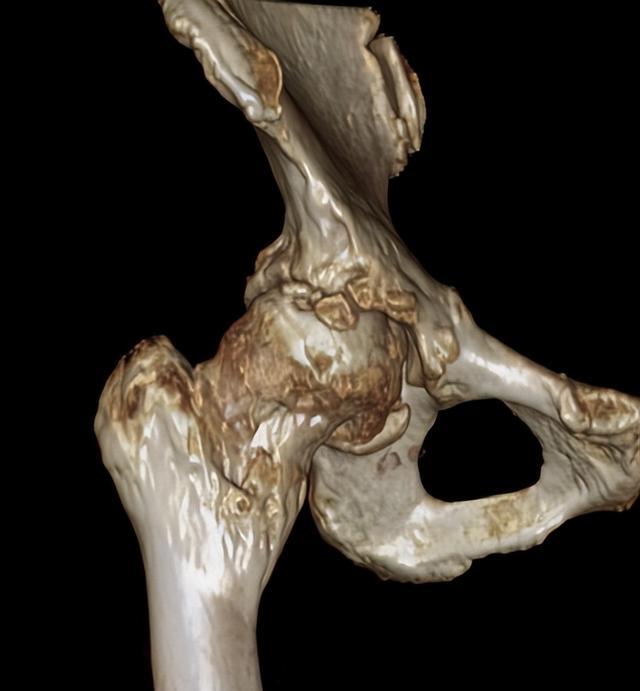

▲术前影像资料(股骨头塌陷、骨质增生)

经进一步影像学检查,接诊的柴志勇副主任医师发现,朱女士股骨头已经出现变形塌陷,髋关节周围出现大量的骨质增伤,关节僵硬,关节间隙狭窄,呈现出典型的股骨头坏死晚期影像学表现,唯有全髋关节置换才能解决他目前的问题。